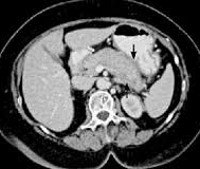

Стандартное исследование подтверждает заболевание только на поздней стадии. При эндоскопическом ультразвуковом исследовании поджелудочной железы визуализируется очаговое или диффузное уплотнение ткани, чередование областей расширения и сужения протока поджелудочной железы («сосискообразная поджелудочная железа»).

Аутоиммунный тип панкреатита характеризуется диффузным увеличением размера органа или наличием ограниченного опухолеподобного образования, деформацией контуров протоков. МРТ поджелудочной железы также используется для контроля эффективности терапии глюкокортикостероидами.